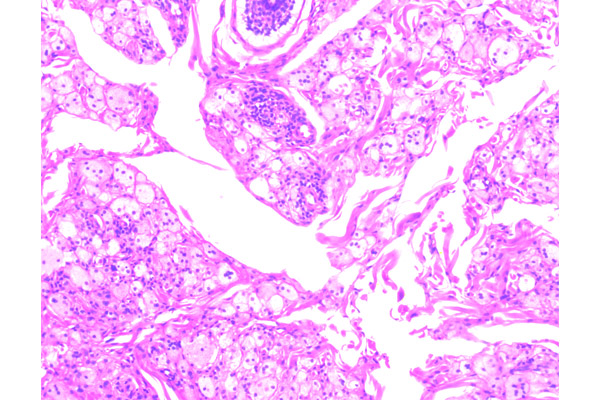

Segmento de piel palpebral, desprovista de anexos pilosebáceos, muestra rectificación del epitelio e hiperpigmentación de la capa basal.

En la dermis se aprecia una gran acumulación de lípidos.

Los lípidos se encuentran en el citoplasma de los macrófagos, acompañados de ocasionales células inflamatorias mononucleares.